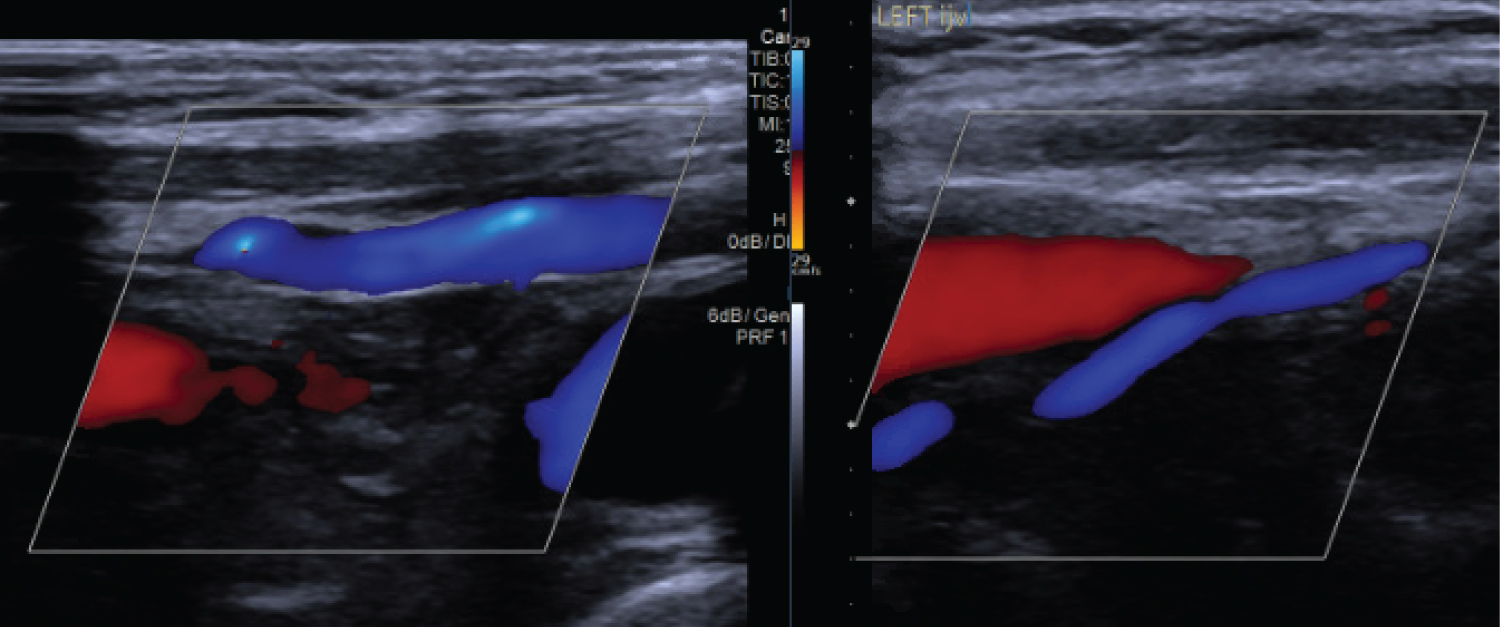

A brain and cervical spine CT angiogram (CTA) was performed as a part of our routine pre-operative planning. Review of this scan in our skull base MDT raised a possibility of bilateral jugular vein obstruction just below the skull base (Figure 2A) with enlarged venous system in the cervical paraspinal muscles (Figure 2B). There was also finding of bilateral elongated styloid processes of 4 cm, with associated bilateral internal jugular vein (IJV) stenosis. The narrowed calibre internal jugular veins continued throughout the neck. The stenosis of the IJVs resulted in a large substantial flow from the sigmoid sinuses into the deep and dilated venous channels in the paraspinal muscle. The concern at this stage was that the paraspinal venous channels were the primary intracranial venous outflow, with potential risks of venous hypertension with brain swelling, and venous infarction in event of any damage during surgical exposure for craniotomy for foramen magnum meningioma. A possible change in surgical approach was considered based on above findings, pending more information. Following discussion with vascular surgery service a doppler ultrasound of neck was performed, which reassuringly demonstrated patency and a reasonable blood flow through both IJVs. There was no evidence of underlying thrombosis (Figure 3). Although this was reassuring, the patient was counselled in detail about small risks of potential venous infarction, surgical access difficulties and incomplete resection.

Figure 3: Right and Left Internal jugular vein Doppler ultrasound showing normal venous flow. View Figure 3